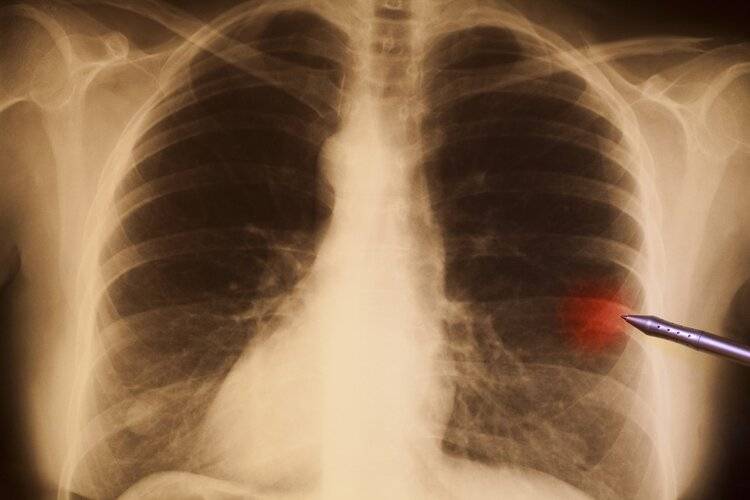

众所周知,雾霾最大的危害就是伤肺,那它会不会诱发严重的肺癌呢?这个问题,今天跟小艾一起探讨一下。

雾霾到底会不会致癌?首先,明确表明雾霾确实是致癌物。世界卫生组织将雾霾列为一级致癌物质 。也就意味着,目前有足够证据表明空气污染和癌症(肺癌)有直接的因果关系。

但大家要明白一点,致癌的因素除了雾霾,还会受到其他因素影响,而且致癌是需要时间性的,它是一个慢性和长期性的过程。

作为国内知名的呼吸疾病专家,钟南山曾对此话题表示:目前有资料明确显示吸烟吸入的二氧化氮与肺癌患病率有密切关系,但是雾霾与肺癌关系几何,需要一个长期的科研调查、采样、跟踪过程,以科学的态度说,目前尚不能得出“空气污染直接导致肺癌”的结论。

这么看来,中国雾霾对肺癌的影响,必须要等到至少10年——20年,才有足够的数据去支撑。